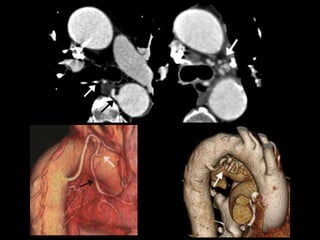

• Otro caso

Varón de 56 años que consulta por hemoptisis

• Otro caso Varónde 56 años que consulta por hemoptisis